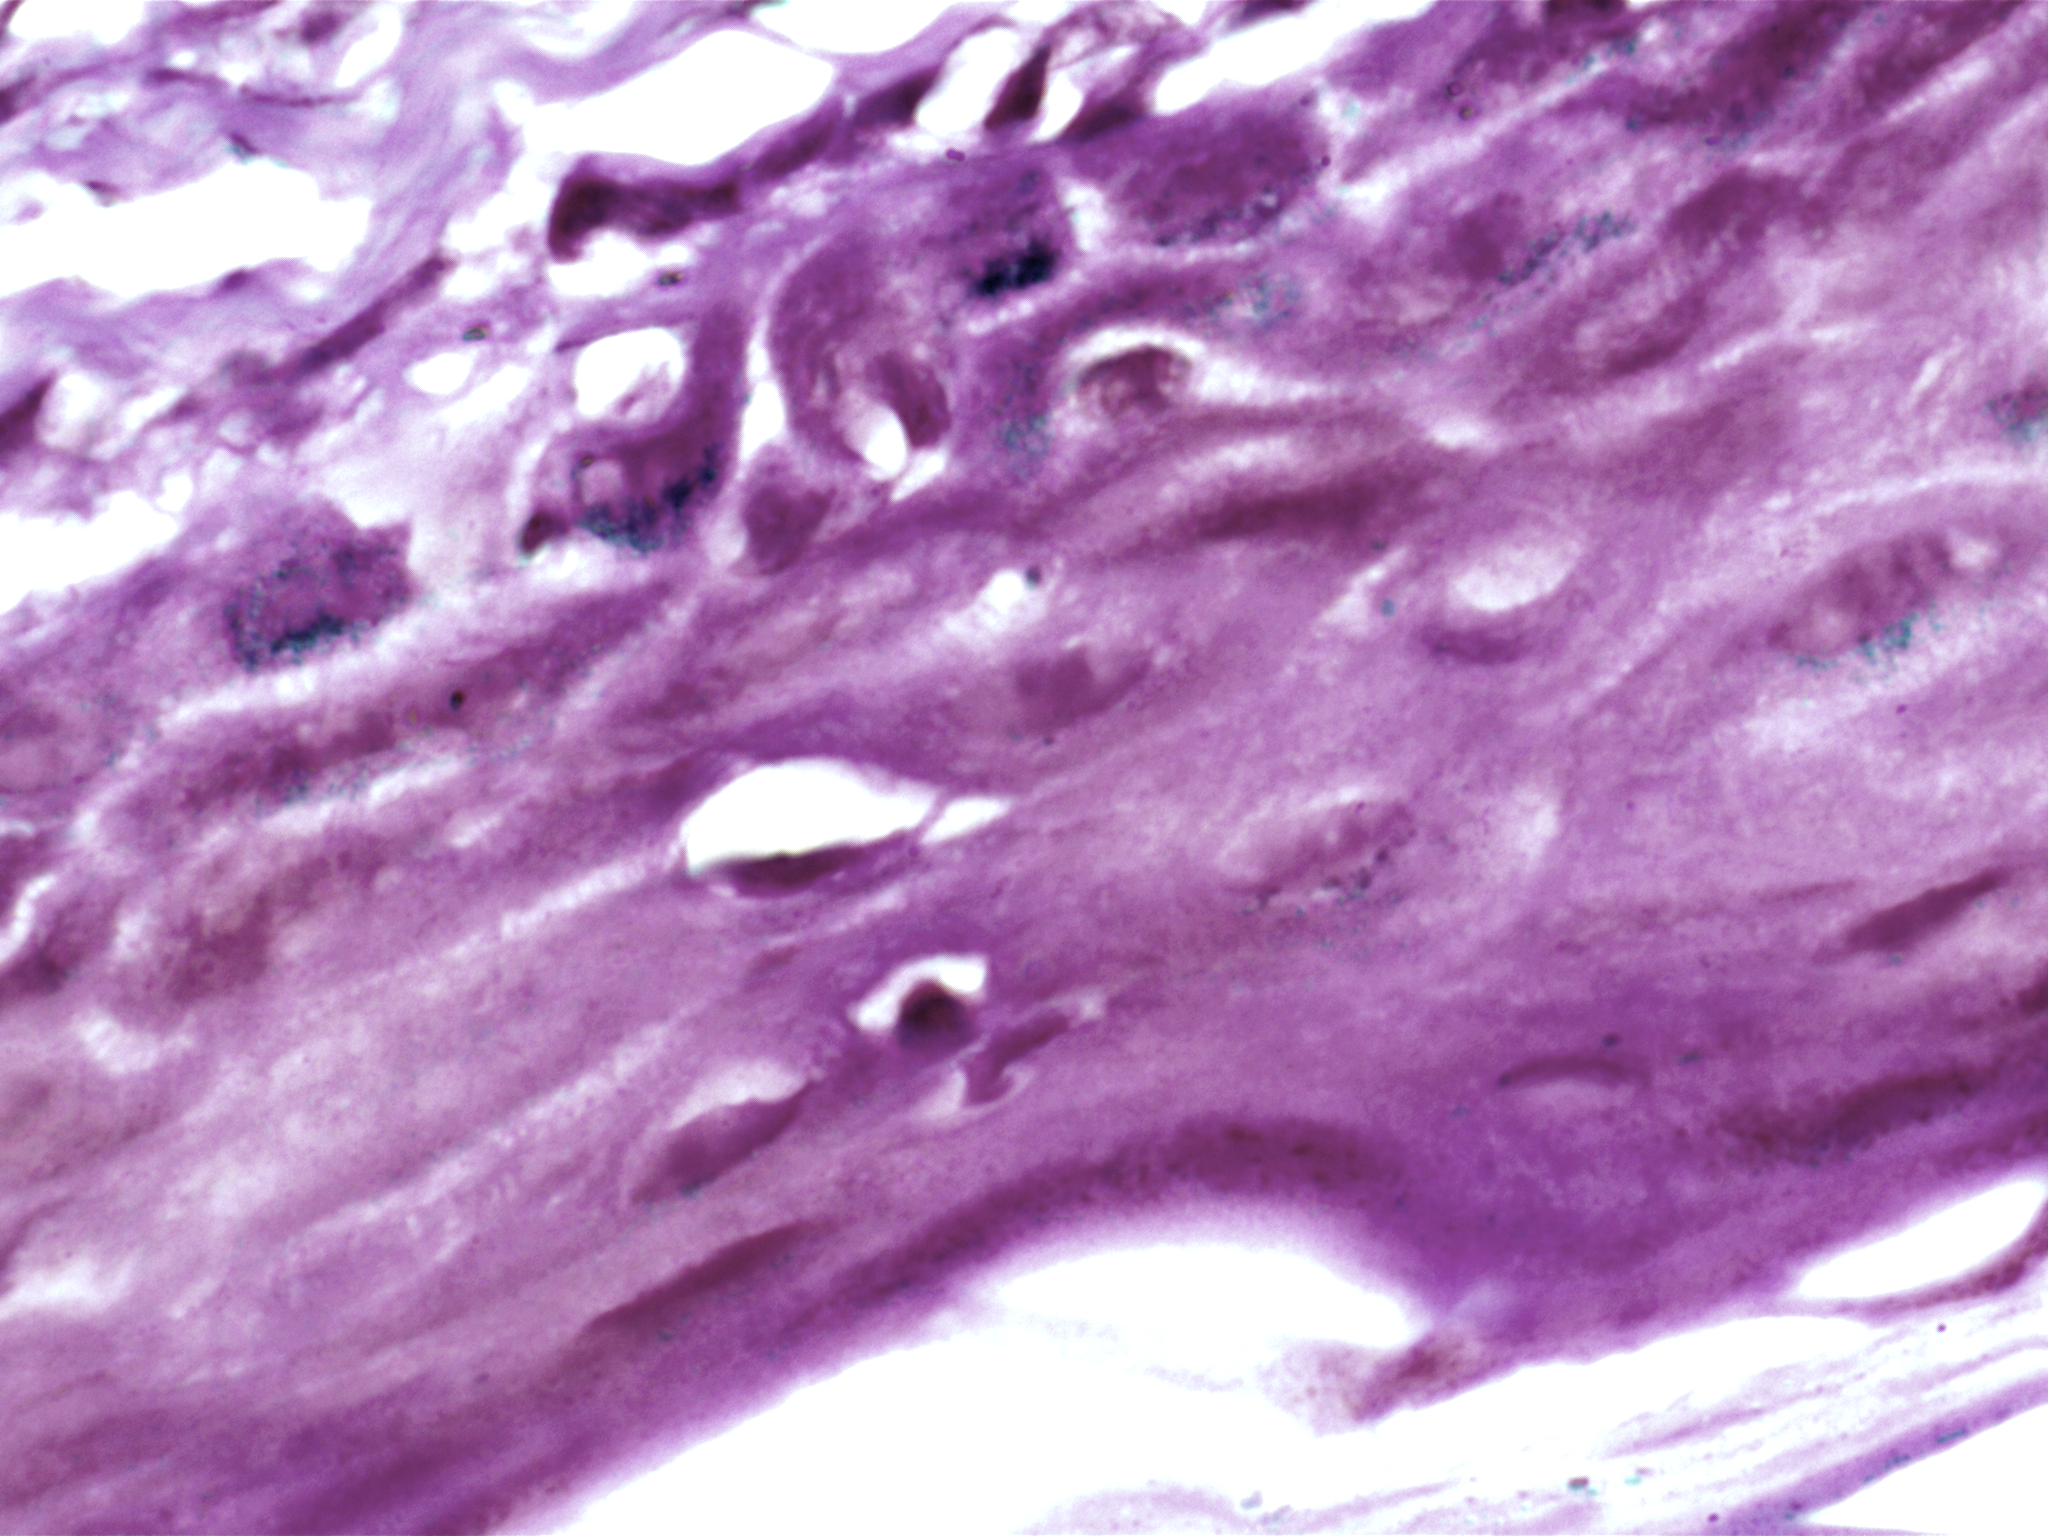

| Description: | Oral cancer is a global health challenge with a difficult histopathological diagnosis. The accurate histopathological interpretation of oral cancer tissue samples remains difficult. However, early diagnosis is very challenging due to a lack of experienced pathologists and inter- observer variability in diagnosis. The application of artificial intelligence (deep learning algorithms) for oral cancer histology images is very promising for rapid diagnosis. However, it requires a quality annotated dataset to build AI models. We present ORCHID (ORal Cancer Histology Image Database), a specialized database generated to advance research in AI-based histology image analytics of oral cancer and precancer. The ORCHID database is an extensive multicenter collection of high-resolution images captured at 1000X effective magnification (100X objective lens), encapsulating various oral cancer and precancer categories, such as oral submucous fibrosis (OSMF) and oral squamous cell carcinoma (OSCC). Additionally, it also contains grade-level sub-classifications for OSCC, such as well- differentiated (WD), moderately-differentiated (MD), and poorly-differentiated (PD). The database seeks to aid in developing innovative artificial intelligence-based rapid diagnostics for OSMF and OSCC, along with subtypes. |

| Imaging Type: | Histopathology (HISTO) |

| The ORCHID database is an extensive multicenter collection of high-resolution images captured at 1000X effective magnification (100X objective lens). Tissue slides were collected with the approval of an ethical committee from the participating hospitals and research institutions. The buccal mucosa tissue samples were collected for three classes, normal, OSMF, and OSCC, with grade-wise annotation from the pathologists at each hospital. Biopsy samples of normal, OSMF and OSCC tissues underwent H&E staining. The staining procedure was conducted either in-house or outsourced to different laboratories. To eliminate staining variations across different laboratories, the preparation of H&E slides involved five histopathology labs, each utilizing their own independently developed and optimized protocols for the staining process. Following staining, the samples were examined under a microscope by a skilled histopathologist to assess cellular morphology, and tissue architecture, and identify any distinctive features or abnormalities specific to each sample type. This evaluation by the histopathologist involved grading the tissue slides for OSCC and OSMF, as well as differentiating between normal and diseased tissue sections. Images were acquired using a 1000X magnification (100X objective) lens from Leedz microimaging (LMI) bright field microscopy. To capture the images consistently, we utilized ToupView imaging software, which was configured for automatic adjustments. This setting applies to both white balance and camera settings, thereby standardizing the image acquisition process across different slides. The images of the H&E stained slides were captured at 1000X magnification(100X objective lens). By setting the ToupView software to automatically adjust white balance and camera settings, we aimed to minimize human intervention and the variability it introduces. This approach ensures that the images are not only consistent but also replicable in different laboratory settings, provided similar equipment and software settings are used. We collected approximately 100–150 images per tissue slide, which were stored in PNG file format. |